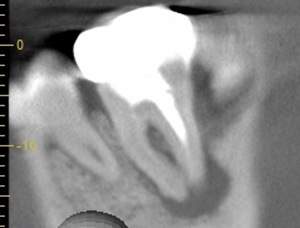

患歯を見極めるためと、状態の悪さをみるため、CTを撮影しました。治療前では上顎洞への大きな炎症が見られます。また、上顎洞底線も無くなっています。また左上の前から4番目の歯の根尖周囲にも透過像が見られます。5番目の歯に関しては根尖が鋭利になっており、根尖性歯周炎によって吸収されたことがわかります。ですので、まず第一の患歯は5番目の歯であるとしました。

治療後3ヶ月経つと上顎洞への炎症も無くなっています。また、上顎洞底線もきれいにみえます。4番目の歯の根尖周囲の透過像もなくなりました。5番目の根尖にまだ透過像がありますが、臨床的症状がないことから、治癒傾向にあるものと判断しました。